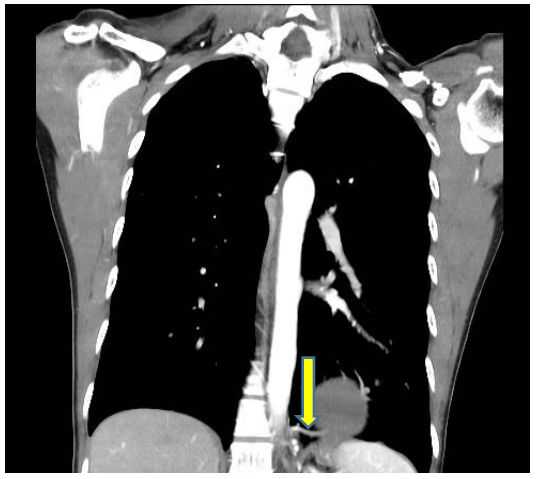

图1肿块边缘多发迂曲血管影,滋养动脉

图2纵隔窗表现

图4隔离肺组织由腹主动脉与胸主动脉共同供血

胸部CT扫描检查无痛苦、创伤小,是目前临床上常用的诊断手段。由于低分辨率平扫不能显示异常血管,难以与其他相关疾病鉴别,导致误诊率高,因此,临床上如怀疑肺隔离症,应予以行胸部增强CT+CTA,以准确发现异常滋养血管。

它可以长成这样↓↓↓

图7左下肺内侧基底段团状密度增高影,内可见不规则含气空腔及气液平